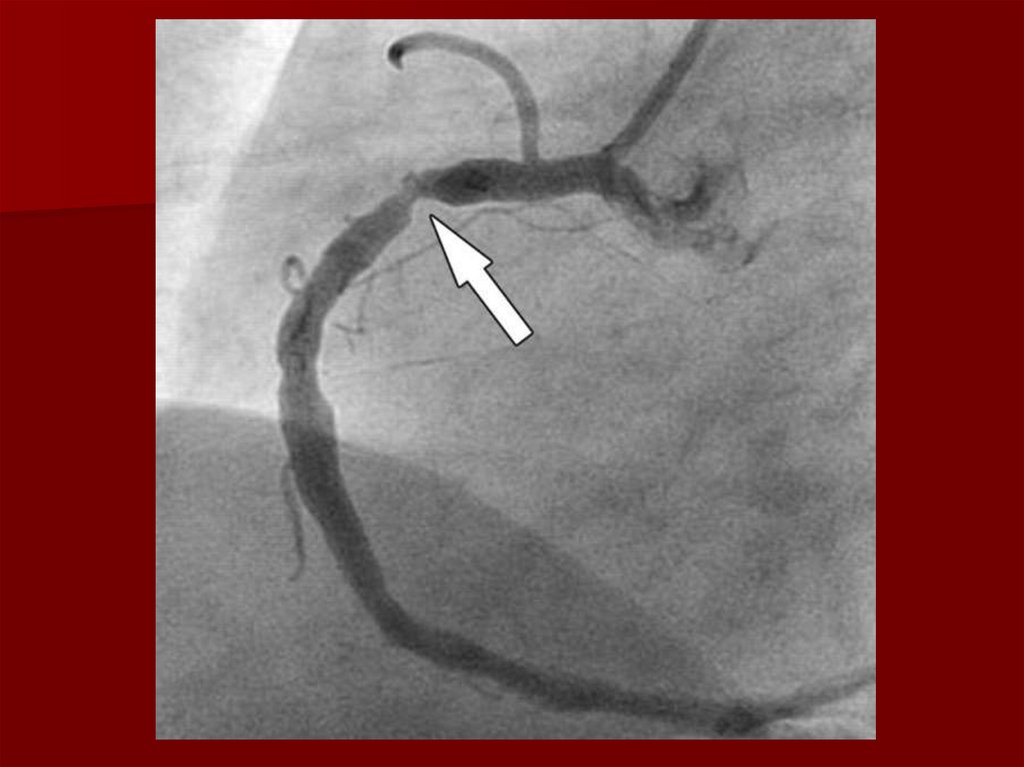

20. Инстументальные методы диагностики

Коронарография

Коронарография (решает только врач исходя из

состояния здоровья пациента).

Хирургическое (ангиопластика,

стентирование, шунтирование)